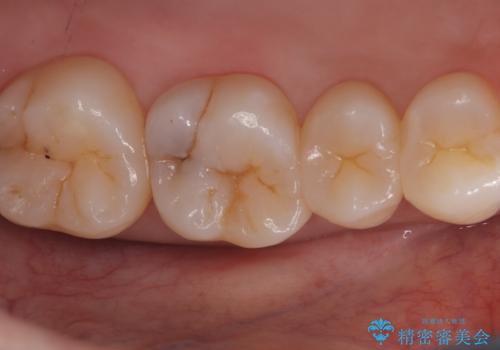

- 主訴:奥歯の噛む面が虫歯になっている。プラスチックの材料で治療可能と言われたが、劣化してまた虫歯になるのが怖いのでセラミックの詰め物にしたい。

咬合面にう蝕があり、CR修復・各種インレーの特徴を説明し、審美性・適合性の良いセラミックインレーでのやり替えとなりました。

咬合面のみのう蝕の場合CR(コンポジットレジン)修復を行うことが多いですが、CRは経年劣化しやすく二次う蝕の可能性を帯びています。それに比べセラミックは着色や収縮が少なく、経年劣化しにくい材料のため、今回はセラミックインレーでの治療となりました。